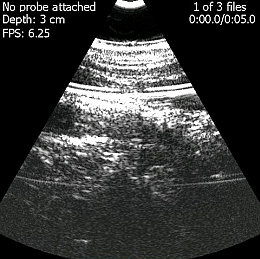

Ultraschall: MobiUS macht stationäres Gerät transportabel (Foto: mobisante.com) |

Mit dem mobilen Computer, der das etwas veraltete Windows Mobile 6.5 als Betriebssystem einsetzt, steuert der Arzt den Scanvorgang. Dieser soll ab Einschaltung von MobiUS in nur 45 Sekunden möglich sein. Das Display liefert auf 4,1 Zoll ein WVGA-Bild von 800x480 Pixeln, die Aufnahmen des Sonographen erreichen eine Auflösung von 480x480 Pixel. Die Abtastung erfolgt in mehreren Tiefenstufen und einer Wandlung von 3,5 bis zwölf MhZ, womit auch kleine Organe betrachtet werden können.